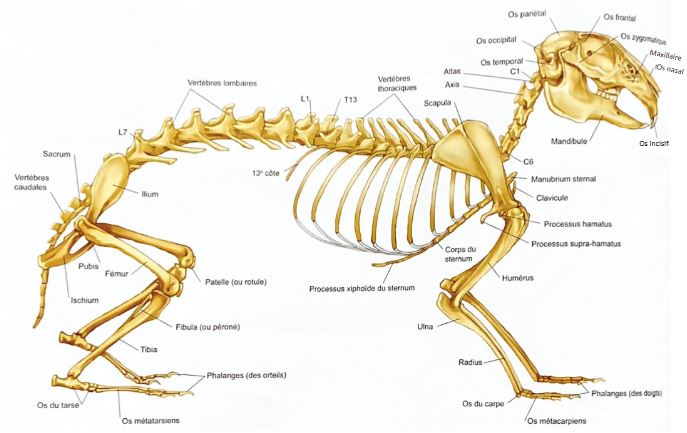

Comme les chiens et les chats, les lapins sont des vertébrés : ils possèdent un squelette osseux. Leur anatomie et leur physiologie osseuse ont souvent été étudiées afin d’être utilisés comme modèle dans la médecine humaine. Ces connaissances sont aujourd’hui très utiles au développement de la médecine des Nouveaux Animaux de Compagnie (NAC), permettant d’affiner la prise en charge des affections osseuses.

Quelles sont les particularités des os du lapin ?

Chez le lapin, le squelette ne représente que 7 à 8 % du poids total du corps. À taille égale, il représente 12 à 13 % du poids corporel chez le chat ! Le squelette des lapins est donc relativement léger, grâce à des os plus fins, et des corticales plus fines que chez les carnivores, à poids équivalent. Il est donc relativement fragile.

Les muscles, quant à eux, sont très développés, représentant 50% du poids total du corps. En particulier les muscles des pattes arrière et du dos, qui représentent respectivement 13% et 9% de la masse musculaire totale. À taille égale, les muscles du dos sont nettement plus développés chez le lapin que chez le chien ou le cheval. Quant aux muscles des pattes arrière, ils sont plus massifs dans la région des membres proche du dos.

Si dans la nature, cette musculature permet une fuite rapide face à un prédateur grâce à une propulsion puissante du corps par les pattes arrière, elle peut être responsable de traumas vertébraux lorsque les lapins sont manipulés sans contention adaptée. En effet, lors de ruade, la masse musculaire peut, en appliquant une force importante et brutale sur les vertèbres lombaires, provoquer une fracture ou une luxation de ces dernières. Il est donc important de toujours bien maintenir le bassin des lapins lorsqu’ils sont portés.